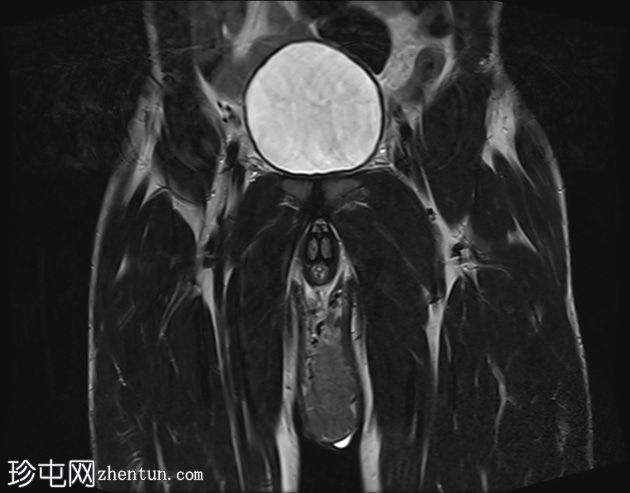

MRI

冠状位

T2加权像

阴囊内睾丸增大,T1加权像上可见分叶状软组织病变,呈中高信号,T2加权像上呈低信号。

轻度双侧鞘膜积液。

本病例表现为双侧睾丸肿胀,影像学特征符合睾丸肾上腺残余肿瘤的典型表现,即T1加权像上呈双侧中高信号,T2加权像上呈低信号。